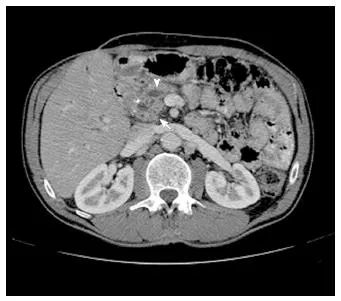

- Diagnosis: CT scan is best for detecting calcifications & ductal dilation ("chain of lakes" appearance). ↓ fecal elastase confirms exocrine insufficiency.

⭐ Amylase and lipase are often normal due to burnout of acinar cells, unlike in acute pancreatitis.